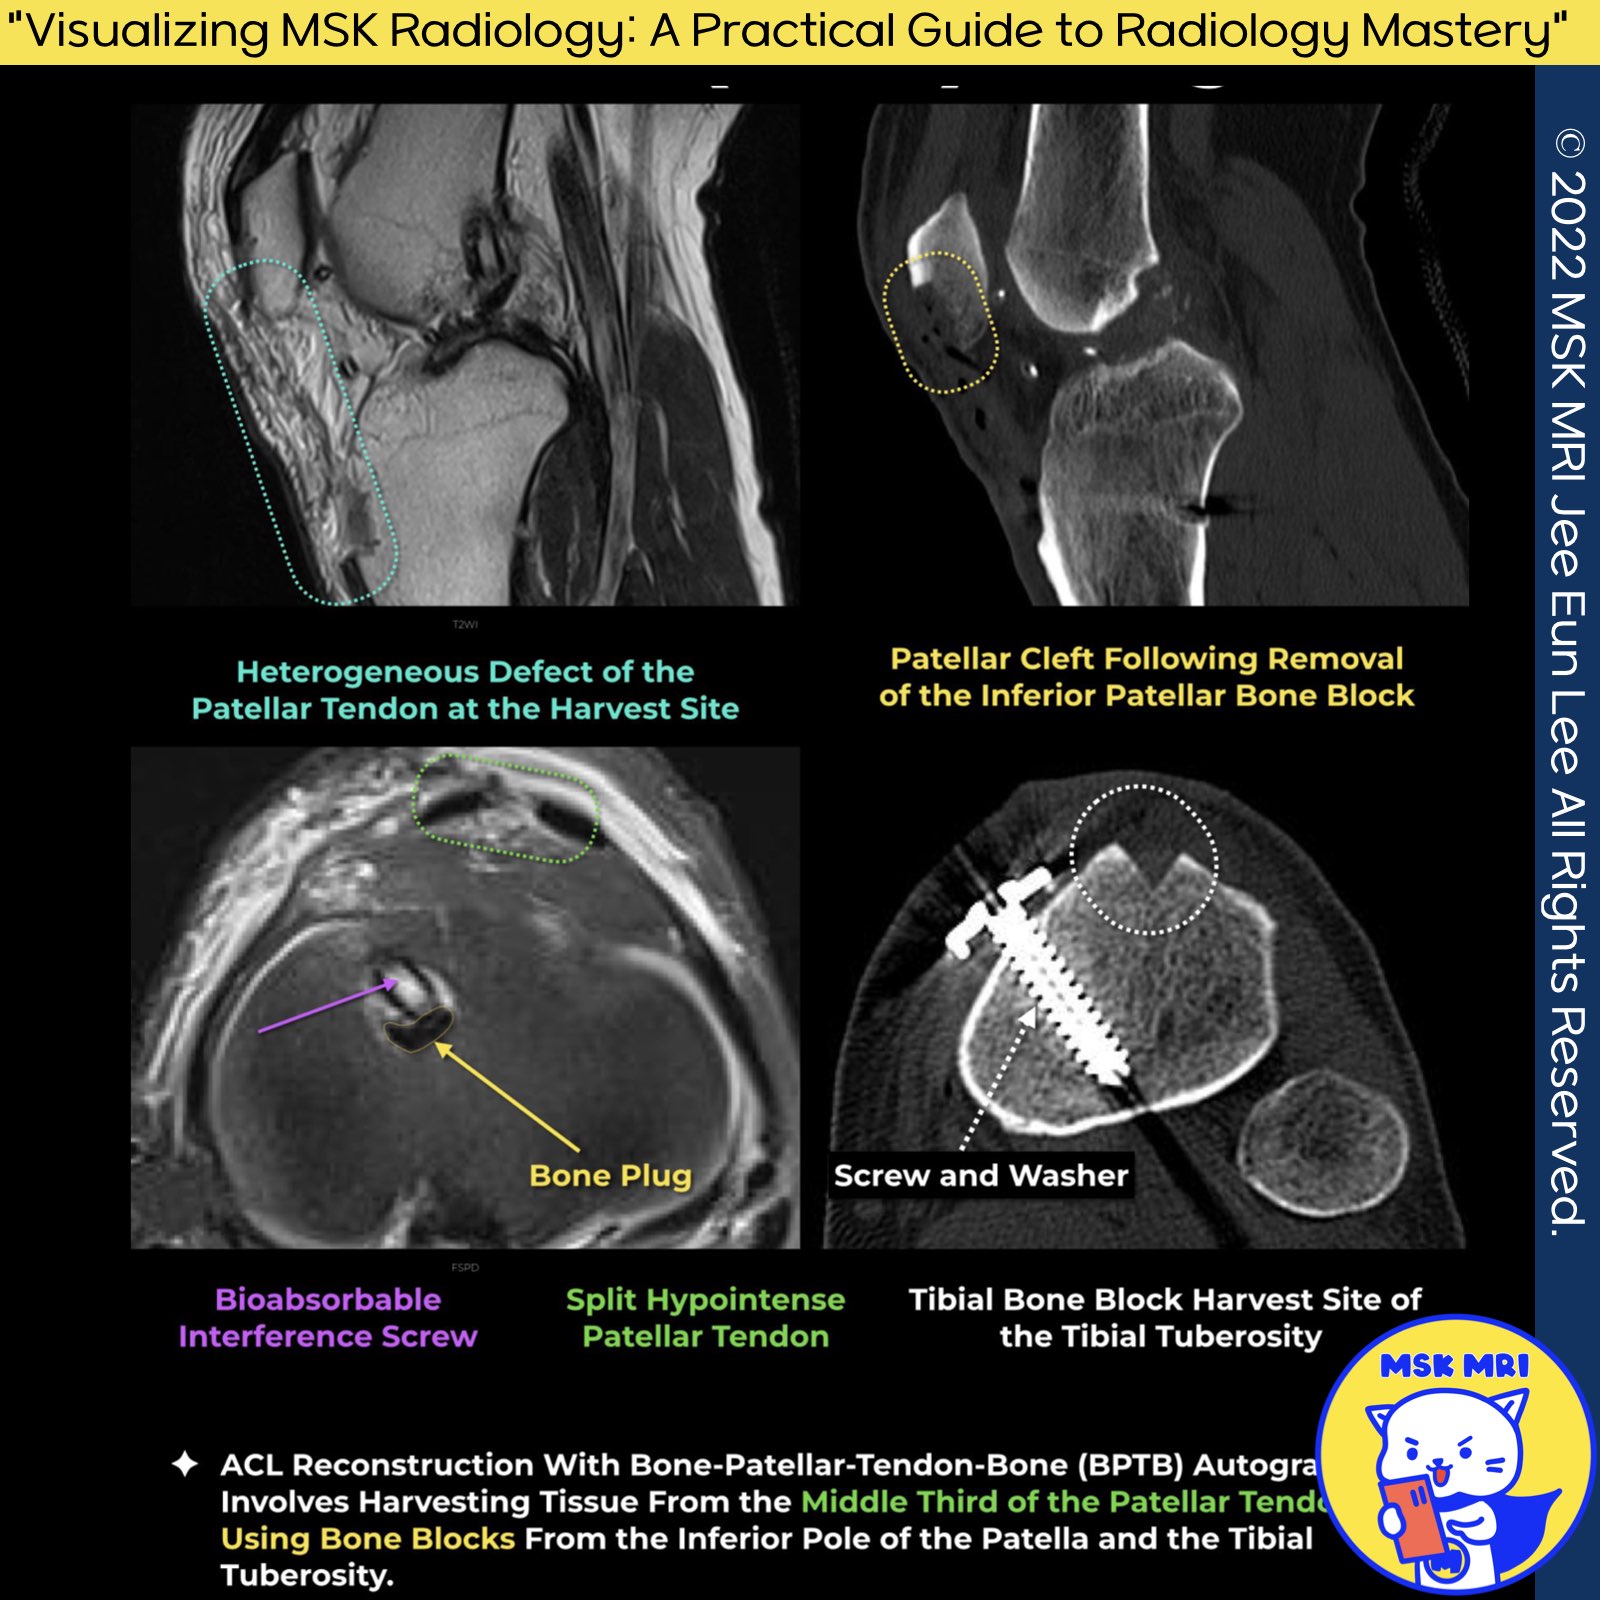

✅ Screw and Washer

- Greater length required to ensure sufficient graft length along the interference screw

- Adequate length necessary for proper fixation and stability

- Additional length required when using a spiked ligament screw washer on the tibial cortex

- Graft must extend out of the tibial tunnel to accommodate the washer